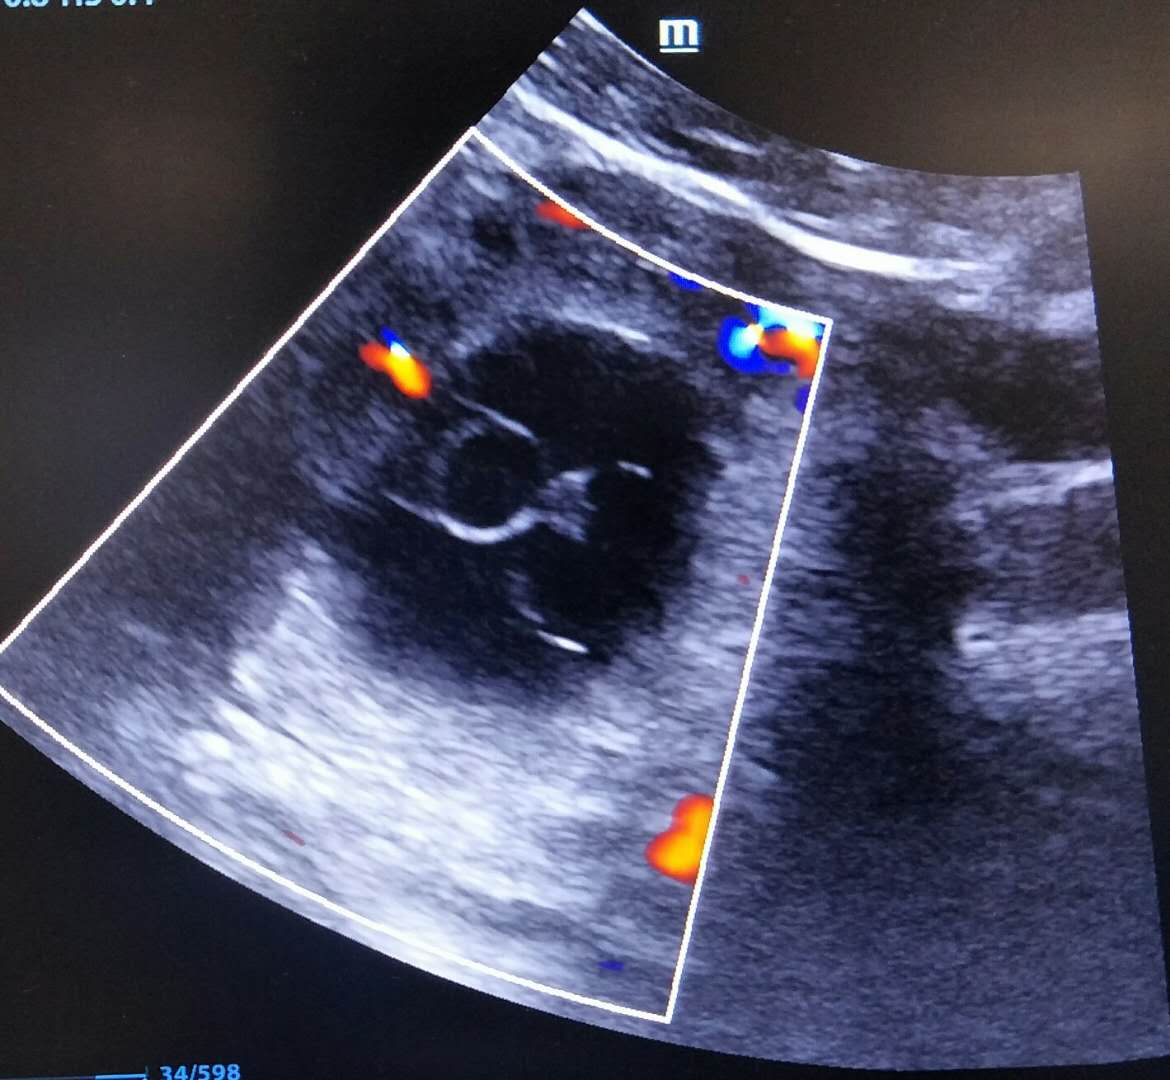

前段一位女士上个月刚上宫内节育器,这个月宫外孕,盆腔腹腔都有出血,已经伴有休克症状了,尿妊娠阳性,彩超检查看到附件区一个孕囊声像。

M代表输卵管妊娠囊,LO代表左侧卵巢